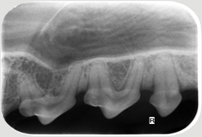

Neben der allgemeinen Untersuchung und der Untersuchung der Zahntaschen mittels Parodontalsonde sind ZAHNRÖNTGEN unumgänglich für eine komplette Diagnostik von Parodontalerkrankungen und bei Zahnresorptionen vor allem bei der Katze (FORL). Dabei werden spezielle Techniken mit Dentalfilmen wie beim Menschen verwendet.

In der Kleintier-Ordination Mittertreffling wird eine moderne digitale Entwicklung verwendet, die die Strahlenbelastung für Ihr Tier verringert. Ohne Zahnröntgen wird das Ausmaß des Knochenverlustes oft unterschätzt und bei der Katze viele Zahnresorptionen übersehen oder unterschätzt. Zudem ist bei einer wie in der Tier-Zahnheilkunde in einer Sitzung durchgeführten Wurzelbehandlung (Endodontie) eine Kontrolle durch Zahnröntgen unbedingt notwendig. Selbst Tumoren können sehr gut erkannt werden und auch die Kontrolle einer Zahnbewegung (Orthodontie) sollte durch Zahnröntgen erfolgen.

Zahnröntgen Oberkiefer Hund P4 Zahnröntgen Unterkiefer Hund normal Zahnröntgen Oberkiefer Hund dreiwurzliger P3